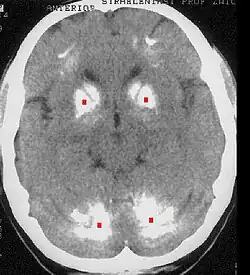

Morbus Fahr im Computertomogramm; Verkalkungen sind rot markiert

Die Fahr-Krankheit oder Morbus Fahr (auch striatodentale Kalzifikation oder Fahr-Syndrom) ist die Bezeichnung für eine Verkalkung der Basalganglien des Gehirns (genaugenommen für eine Kalzinose zwischen Corpus striatum and Nucleus dentatus), welche nicht auf arteriosklerotische Prozesse zurückzuführen ist. Die Erkrankung ist nach Theodor Fahr (1877–1945) benannt, der sie 1930 beschrieb. Die Namensgebung ist umstritten, da sie verschiedene Krankheiten vermischt.